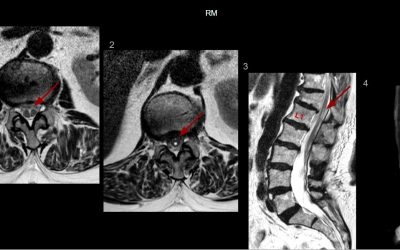

Caso del mes Enero 2026

« Todos los casosAutores Javier Pardo Maiza, Joan Carreres Polo, David Castro Vidal, Pablo García...